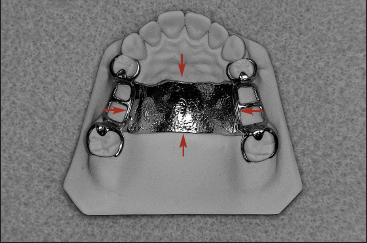

Unlike extracoronal retainers, intracoronal retainers are contained entirely within the contours of a clinical crown (Fig 1-4). Consequently, the use of intracoronal retainers generally requires the fabrication of two or more specially designed, complete-coverage crowns. In most instances, retention of intracoronal removable partial dentures is dependent upon exact parallelism of the retentive assemblies. Each assembly consists of two parts, commonly termed matrix (“female”) and patrix (“male”). Figure 1-5 illustrates the joining of a patrix and matrix to form a functional retentive unit. When a dislodging force is applied to the removable partial denture, binding occurs between the external walls of the patrix and the internal walls of the matrix. This binding results in retention of the prosthesis.

Fig 1-4 An intracoronal retainer lies within the contours of the clinical crown. An intracoronal retainer consists of a matrix or “female” component (right) and a patrix or “male” component (left).